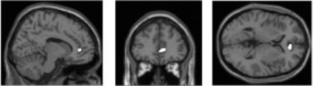

La densidad de materia gris en el córtex del cíngulo anterior está relacionada con la exposición a múltiples dispositivos multimedia. Fuente: Universidad de Sussex.

Los investigadores del Centro Sackler para la Ciencia de la Conciencia, de la Universidad de Sussex, utilizaron imágenes de resonancia magnética funcional (fMRI) para observar las estructuras cerebrales de 75 adultos, todos los cuales habían respondido un cuestionario sobre su uso y consumo de dispositivos multimedia, incluyendo teléfonos móviles y ordenadores, así como prensa de papel y televisión.

Observaron que, independientemente de los rasgos de personalidad individuales, las personas que utilizan un mayor número de dispositivos de este tipo al mismo tiempo tenían también menor densidad de materia gris en la parte del cerebro conocida como córtex del cíngulo anterior (CCA), región especialmente responsable de las funciones de control cognitivo y emocional.